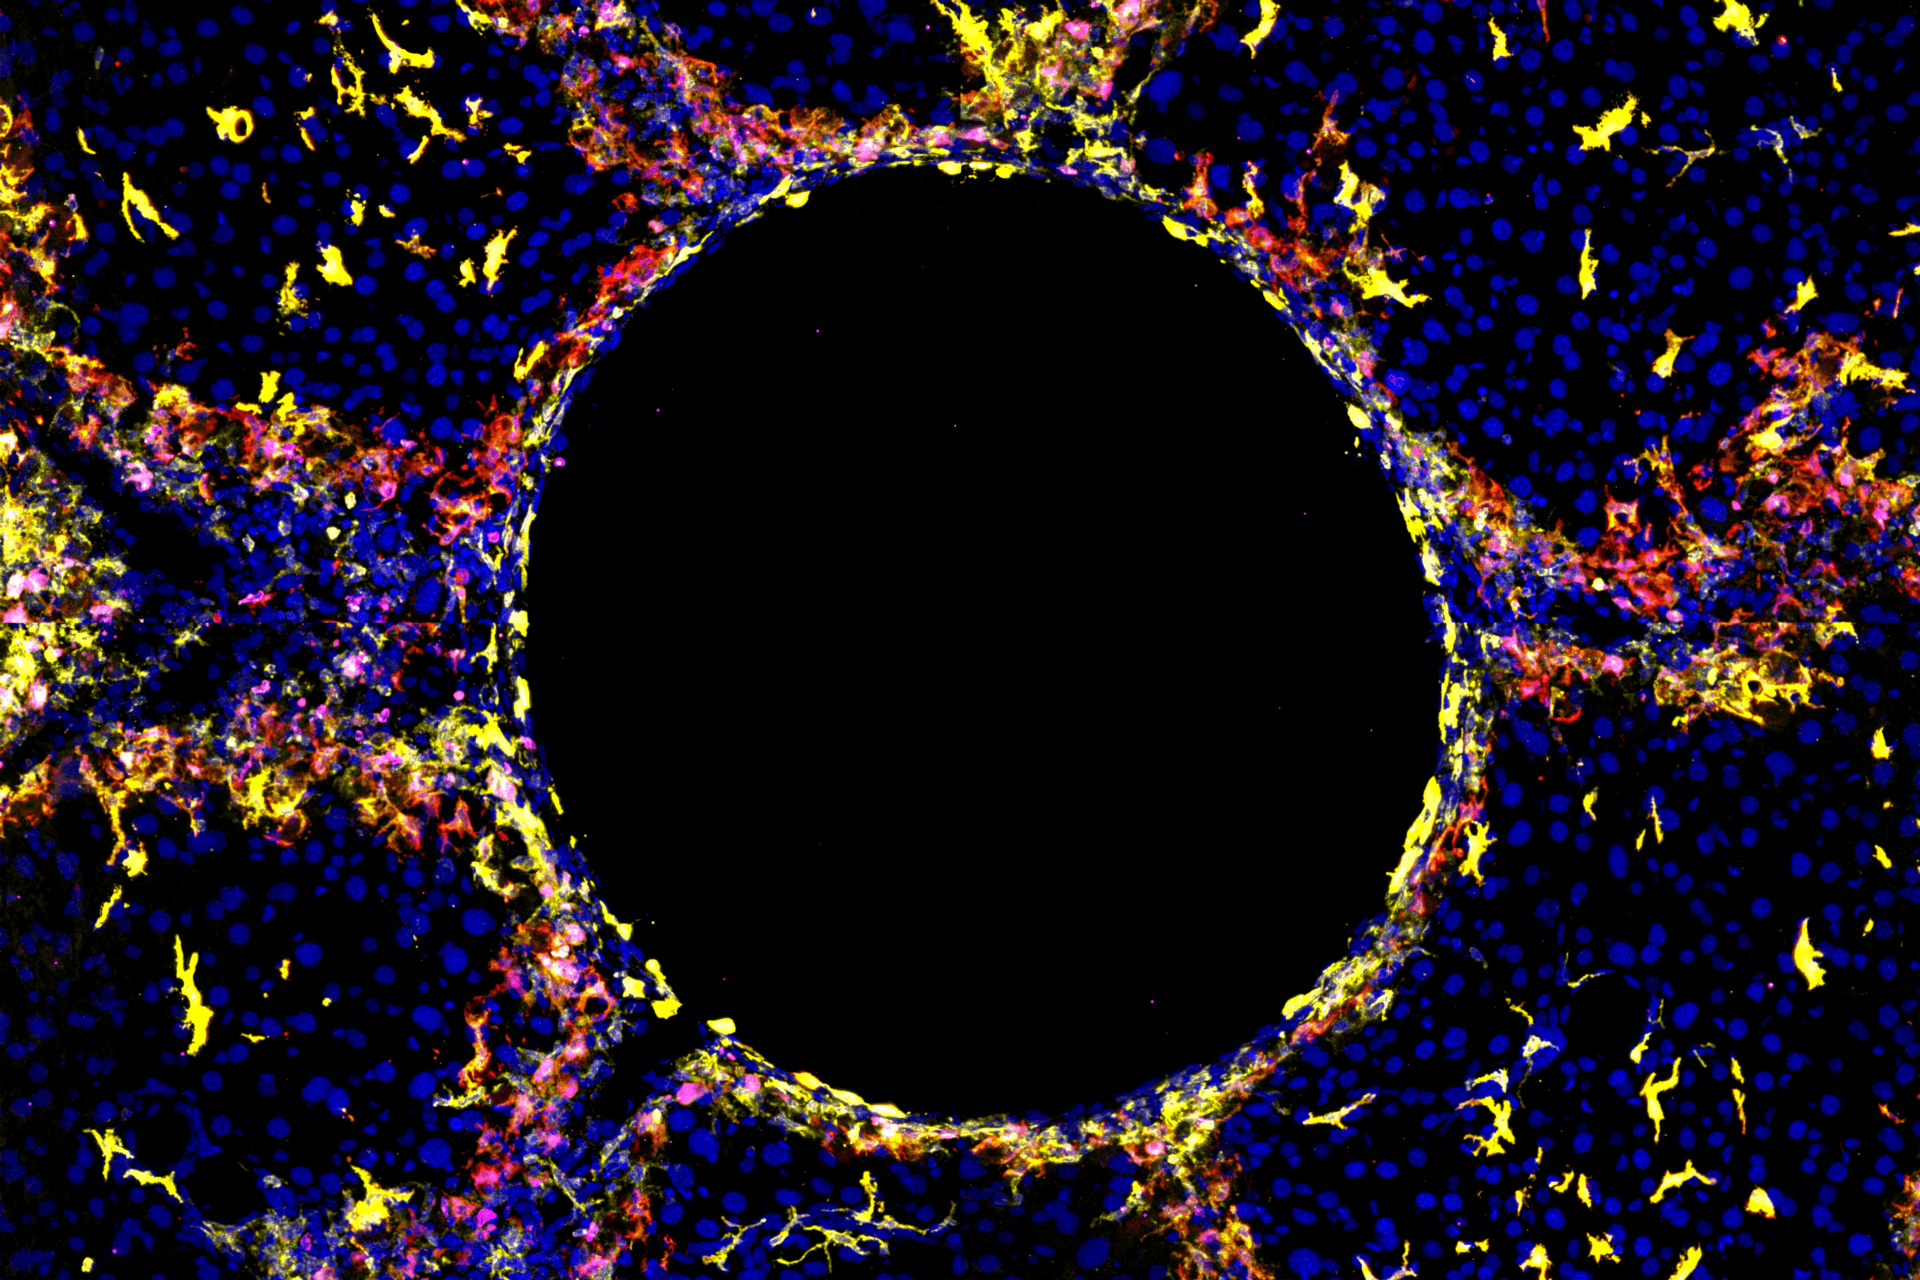

“We used several advanced research methods, such as single-cell RNA sequencing and spatial transcriptomics, to investigate the heterogeneity, locations, and functions of hepatic macrophages in multiple injury settings,” says Dr. Ania Bujko, from the Scott lab and co-first author of the study, “this allowed us to identify similar populations of LAMs and LAM-like KCs irrespective of the injury type, which were found specifically at the site of injury. This finding was exciting as it suggests these cells may be useful therapeutic targets across various liver diseases.”